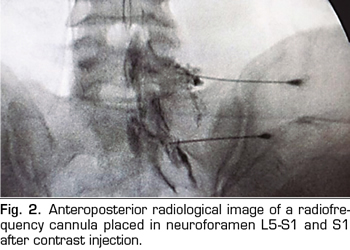

The procedure was performed in the surgical room in ventral decubitus position. A peripheral venous catheter and standard monitoring were placed. The C-shaped arch was used for the location of the DRGs through the anteroposterior, oblique and profile approaches (Figures 1 and 2). A Cosman G4 radiofrequency generator was used. Radiofrequency cannulae number 22 or 20, 10 or 15 cm length respectively, were used, based on the patient’s size, with 1 cm of active tip. The radiofrequency cannula was placed on the anterior-superior side or roof of the selected neuroforamens (Figure 1). In the case of S1, the cannula was placed in the first sacral foramen and the radiofrequency of the nerve root was performed, instead of approaching the dorsal root ganglion through the sacrum, because this is considered excessively invasive. The needle was deepened to an imaginary line located in the middle of the thickness of the sacrum (Figure 2).